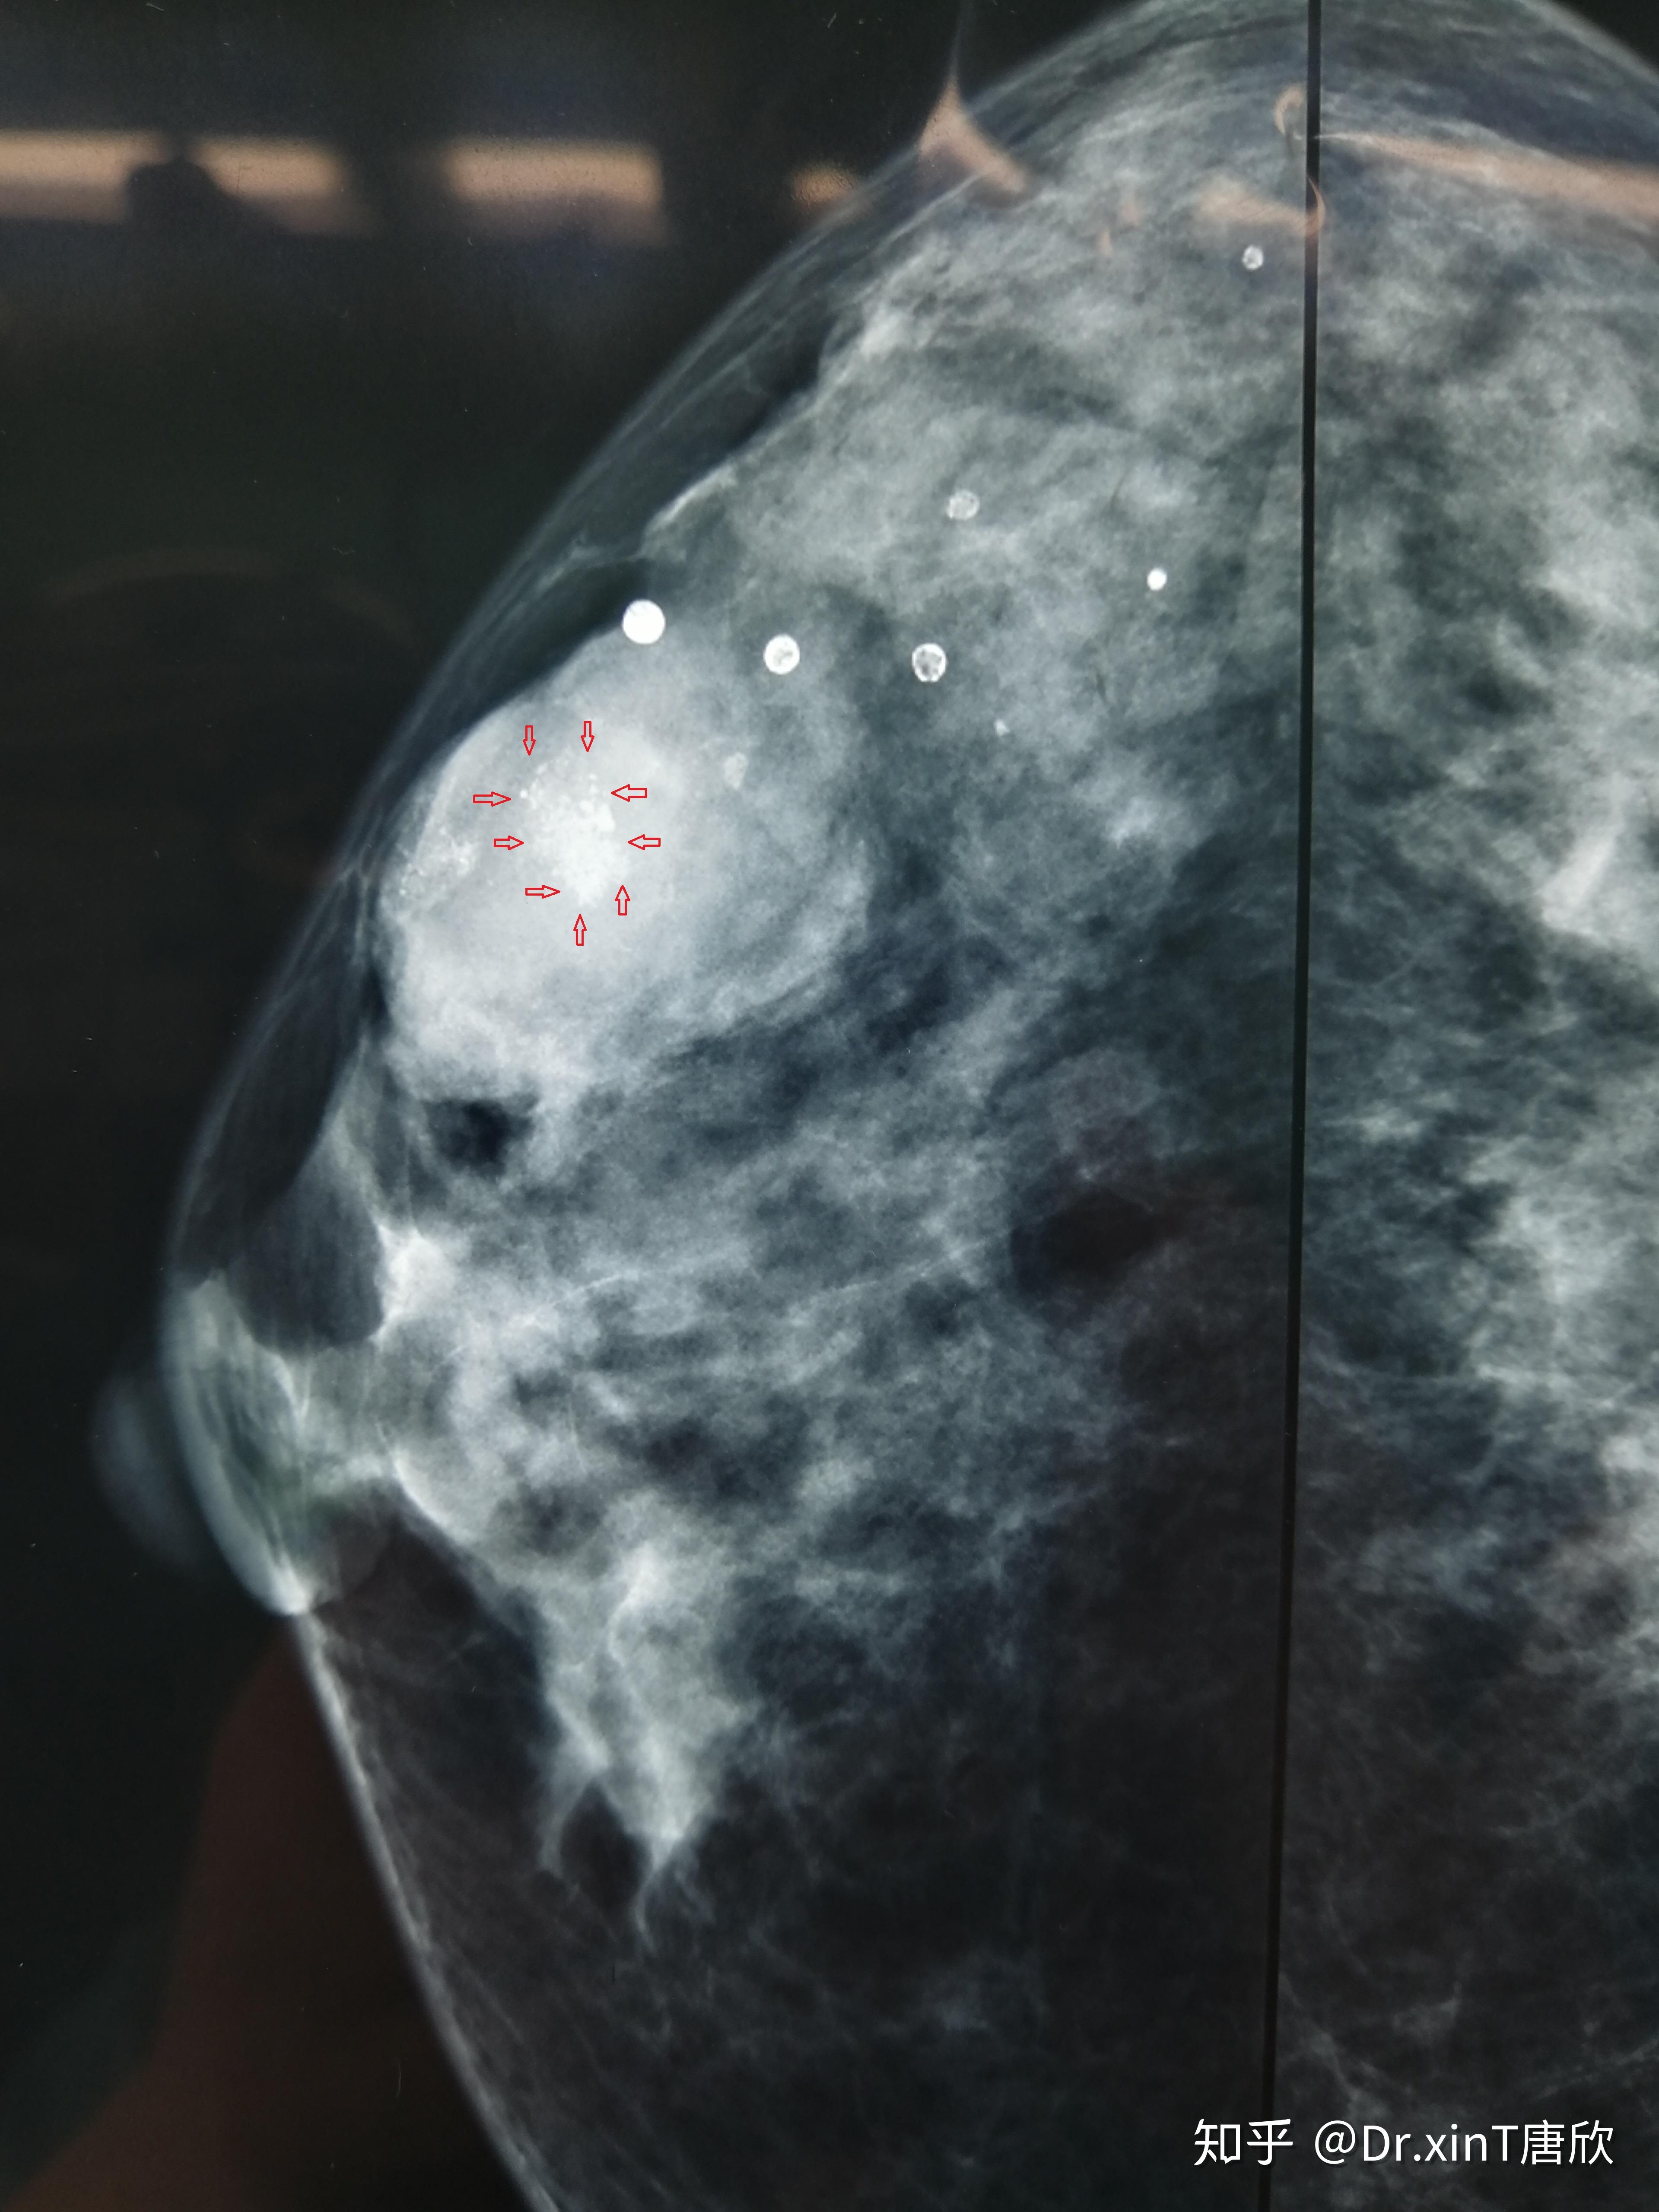

明显的肿块影,以及肿物内的不规则泥沙样钙化(红色箭头内)术前钼靶:术

第三个病人,钼靶高度提示恶性病变,旋切后病理提示,浸润性乳腺癌!